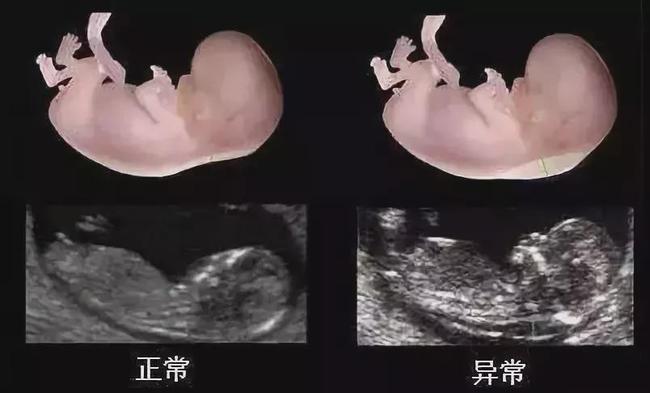

nt检查会在11周~13周,因为患唐氏症的胎儿会有皮下积水的情况出现,此

NT检查正常图片

nt检查图片